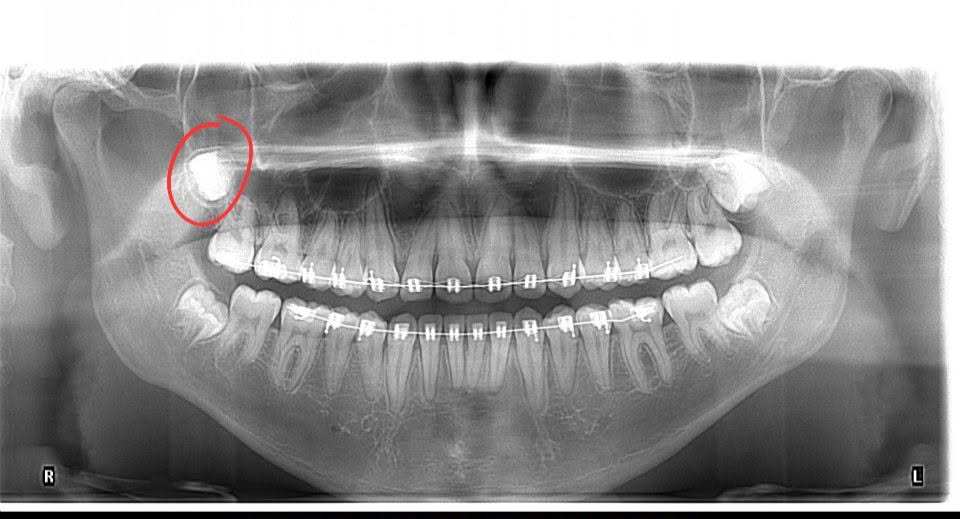

DESPUÉS · 17 AÑOS

Radiografía panorámica a los 17 años mostrando cordal desplazada al cuello

Imagen derecha (17 años): Tras el intento fallido, el dentista general — sin la destreza ni el instrumental adecuado — aplicó fuerza desmedida, fracturó la zona y empujó la cordal hacia espacios anatómicos profundos del cuello. El círculo rojo muestra exactamente dónde quedó atrapada: rodeada de nervios vitales y vías respiratorias.

Hoy, este joven padece problemas respiratorios y secuelas severas permanentes. Lo que debía ser un procedimiento de 30 minutos se convirtió en una pesadilla. Ahora necesita cirugía reconstructiva hospitalaria de altísima complejidad — cuyo costo es monumentalmente superior al de la extracción original. Lo barato le salió increíblemente caro.

Esto NO ocurrió en nuestra clínica. En Bocas y Boquitas toda cirugía es realizada exclusivamente por cirujanos orales y maxilofaciales de élite. Cosas como esta simplemente no pasan aquí. En salud, ir a la segura no es un lujo — es lo mínimo.